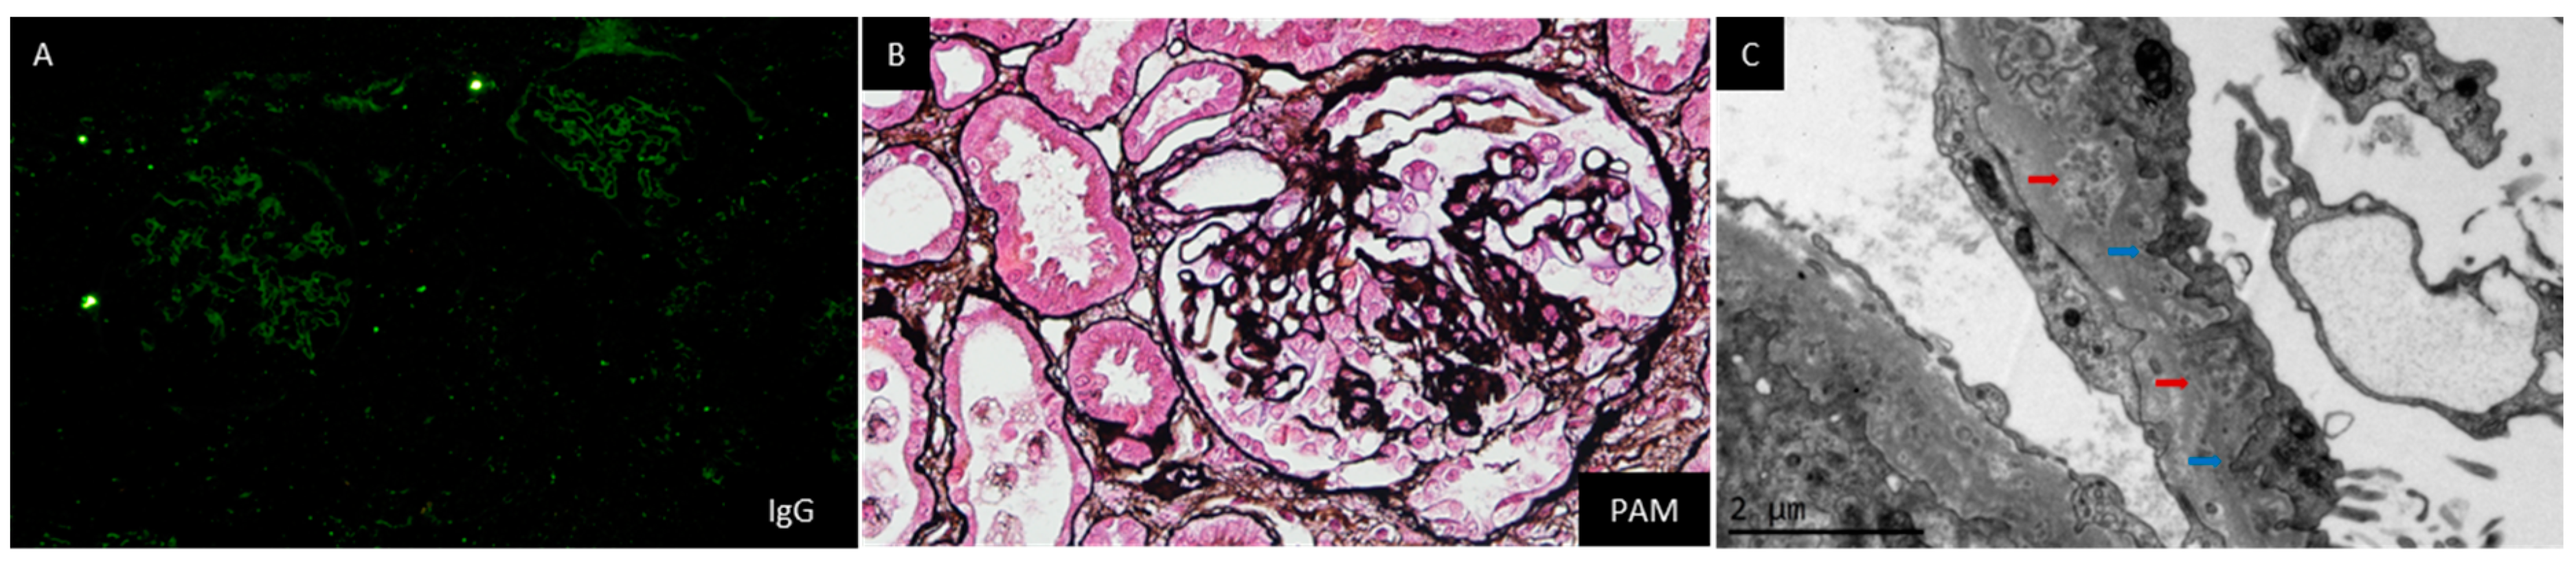

| Case No | Sex | Age | Renal Pathology | ||||||||

|---|---|---|---|---|---|---|---|---|---|---|---|

| IF Staining | Hypercellularity | Mesangial Deposit | GBM Thickening | FPE | Microspheres | Microtubules | Dense Deposit | LM Manifestations | |||

| 1 [2] | M | 31 | All negative | Absent | Mild | Present | Present | Present | Absent | Absent | MGA |

| 2 [2] | F | 37 | G, A, C3, C1q | Absent | Mild | Present | Present | Present | Present | Absent | LN Class II |

| 3 [2] | F | 40 | G, A, C3, C1q | NR | Mild | Present | Present | Present | Present | Absent | LN Class II |

| 4 [2] | F | 30 | G, A, C3, C1q, C5b-9 | Present | Mild | Present | Present | Present | Absent | Mesangium, subendothelial | LN Class II |

| 5 [2] | F | 61 | G, M, C1q | Absent | Mild | Present | Present | Present | Absent | Present | LN Class II |

| 6 [2] | F | 29 | All negative | Absent | Absent | Present | Present | Present | Present | Absent | MN |

| 7 [2] | F | 46 | All negative | Absent | Absent | Present | Present | Present | Present | Absent | MN |

| 8 [2] | F | 27 | G, A, M, C3, C1q, C5b-9 | Absent | Absent | Present | Present | Present | Present | GBM, subendothelial, subepithelial | LN Class V |

| 9 [2] | M | 53 | All negative | Absent | Absent | Present | Present | Present | Present | Absent | MN |

| 10 [2] | F | 23 | G | Present | Mild | Present | Present | Present | Present | GBM, subendothelial, subepithelial | LN Class V |

| 11 [2] | F | 31 | G | Absent | Absent | Present | Present | Present | Present | GBM | LN Class V |

| 12 [2] | F | 24 | G, M, C1q | Mild | Mild | Present | Present | Present | Present | GBM | LN Class V |

| 13 [2] | M | 49 | G, A | Present | Present | Present | Present | Absent | Present | Absent | MPGN (Type 3) |

| 14 [2] | F | 20 | G | Absent | Absent | Present | NR | Present | Absent | GBM | MGA |

| 15 [2] | F | 47 | G, A, M | Absent | Absent | Present | NR | Present | Absent | GBM | MGA |

| 16 [2] | F | 51 | All negative | Absent | Absent | Present | Present | Present | Absent | Absent | MGA |

| 17 [2] | F | 30 | G | Absent | Absent | Present | Present | Present | Absent | Absent | MGA |

| 18 [2] | F | 54 | All negative | Present | Present | Present | Present | Present | Absent | Absent | FSGS |

| 19 [2] | F | 57 | All negative | Absent | Absent | Present | Present | Present | Absent | Absent | FSGS |

| 20 [2] | M | 45 | G, A, C3 | Absent | Present | Present | Present | Present | Present | Absent | FSGS |

| 21 [2] | F | 42 | G | Present | Absent | Present | Present | Present | Absent | Absent | FSGS + MN |

| 22 [2] | F | 69 | G, A, M, C3 | Absent | Absent | Present | Present | Present | Absent | Absent | MN |

| 23 [2] | M | 46 | G | Absent | Absent | Present | Present | Present | Present | Absent | MN |

| 24 [2] | M | 59 | M | Absent | Absent | Present | Present | Present | Absent | Absent | MN |

| 25 [2] | F | 45 | G, A, C3 | Absent | Absent | Present | Present | Present | Present | Absent | MN |

| 26 [3] | M | 4 | All negative | NR | NR | Present | Present | Present | Absent | Absent | Focal or global sclerosis |

| 27 [4] | F | 61 | M, C3 | Present | Present | Present | Present | Present | Absent | Absent | LN |

| 28 [5] | F | 45 | G, C3 | Absent | Absent | Present | Present | Present | Absent | Absent | MN |

| 29 [6] | F | 33 | M, G, C1q, C3 | Mild | Mild | Present | Present | Present | Absent | Mesangium, subepithelial | Proliferative glomerulonephritis |

| 30 [7] | F | 27 | M | Present | Mild | Present | Present | Present | Absent | Absent | Chronic interstitial nephritis |

| 31 [7] | F | 23 | M | Absent | Absent | Present | Present | Present | Absent | Absent | MGA |

| 32 [8] | F | 14 | M, C3, C1q | Absence | Absence | Absent | Presence | Present | Absent | Absent | FSGS |

| 33 [9] | F | 44 | M | Absent | Absent | Present | Present | Present | Present | Mesangium, intramembrane | MGA |

| 34 [11] | F | 52 | All negative | Absent | Absent | Absent | Present | Present | Present | Absent | Global and segmental sclerosis |

| 35 [12] | F | 52 | All negative | NR | NR | Present | Present | Present | Absent | Absent | MGA |

| 36 [13] | M | 79 | All negative | Absent | Absent | Present | Present | Present | Absent | Absent | MN |

| 37 [14] | F | 38 | All negative | Absent | Present | Present | Present | Present | Present | Absent | FSGS |

| 38 [15] | F | 35 | Full house pattern, faint IgG | Present | Mild | Present | Present | Present | Present | Mesangium | LN Class II |

| 39 [16] | F | 60 | G, M, A, C3, PLA2r | Absent | Mild | Absent | Present | Present | Present | Subepithelial | MN |

| 40 [17] | F | 56 | All negative | Absent | Absent | Present | Present | Absent | Absent | Absent | Acute tubular injury |

| 41 | F | 26 | G, M | Mild | Present | Present | Present | Present | Absent | Present | FSGS |

| 42 | M | 47 | G | Mild | Absent | Present | Present | Present | Absent | Absent | FSGS |

| 43 | F | 48 | A, M | None | Present | Present | Present | Present | Absent | Absent | MN |

| 44 | F | 57 | All negative | Absent | Mild | Mild | Present | Present | Present | Absent | MGA |